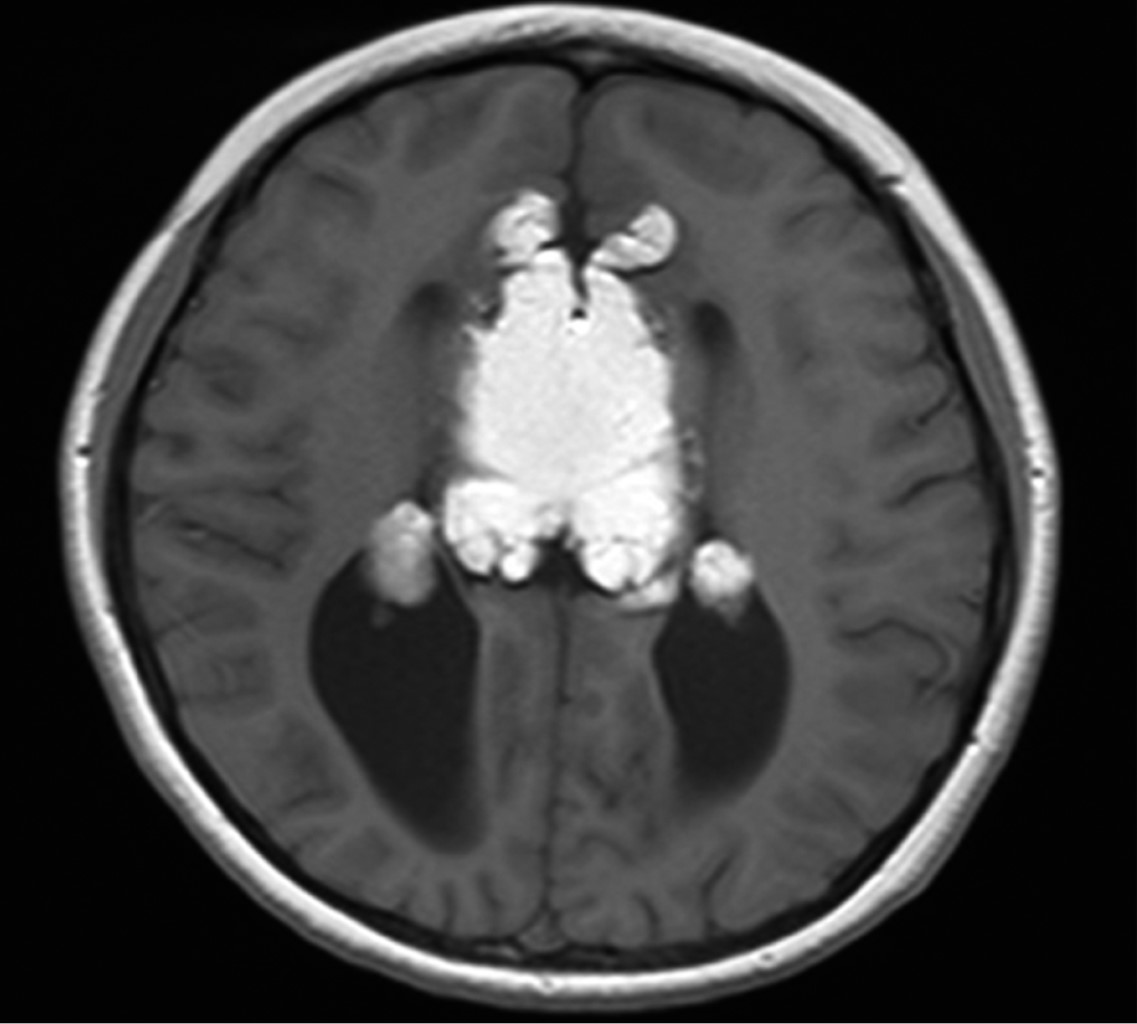

Masculino de siete años edad con antecedente de cefalea, muestra deficiencias en la coordinación motora, equilibrio y lenguaje expresivo. Acude a consulta en medio institucional, donde médico tratante solicita como estudio de abordaje inicial resonancia magnética de encéfalo, en la que se observan cuernos frontales pequeños con dilatación de los trígonos y cuernos occipitales identificando los signos radiológicos en cortes axiales "carro de carreras" (Figura 1) y en cortes coronales "cabeza de alce" (Figura 2). Lo antes descrito se relaciona con disgenesia del cuerpo calloso, la cual se corrobora en cortes sagitales donde no se identifica en la línea media el cuerpo calloso. Además, se identifica masa ubicada en topografía pericallosa de localización anterior, centrada hacia la fisura interhemisférica, lesión de forma irregular de comportamiento hiperintenso en T1 (Figura 1) y T2 (Figura 2), que suprime en secuencia de supresión grasa (Figura 3) y que mide aproximadamente 2.4 × 3.4 × 5.4 cm de diámetro máximo en sus ejes laterolateral, cefalocaudal y rostroventral, respectivamente.

Figura 2